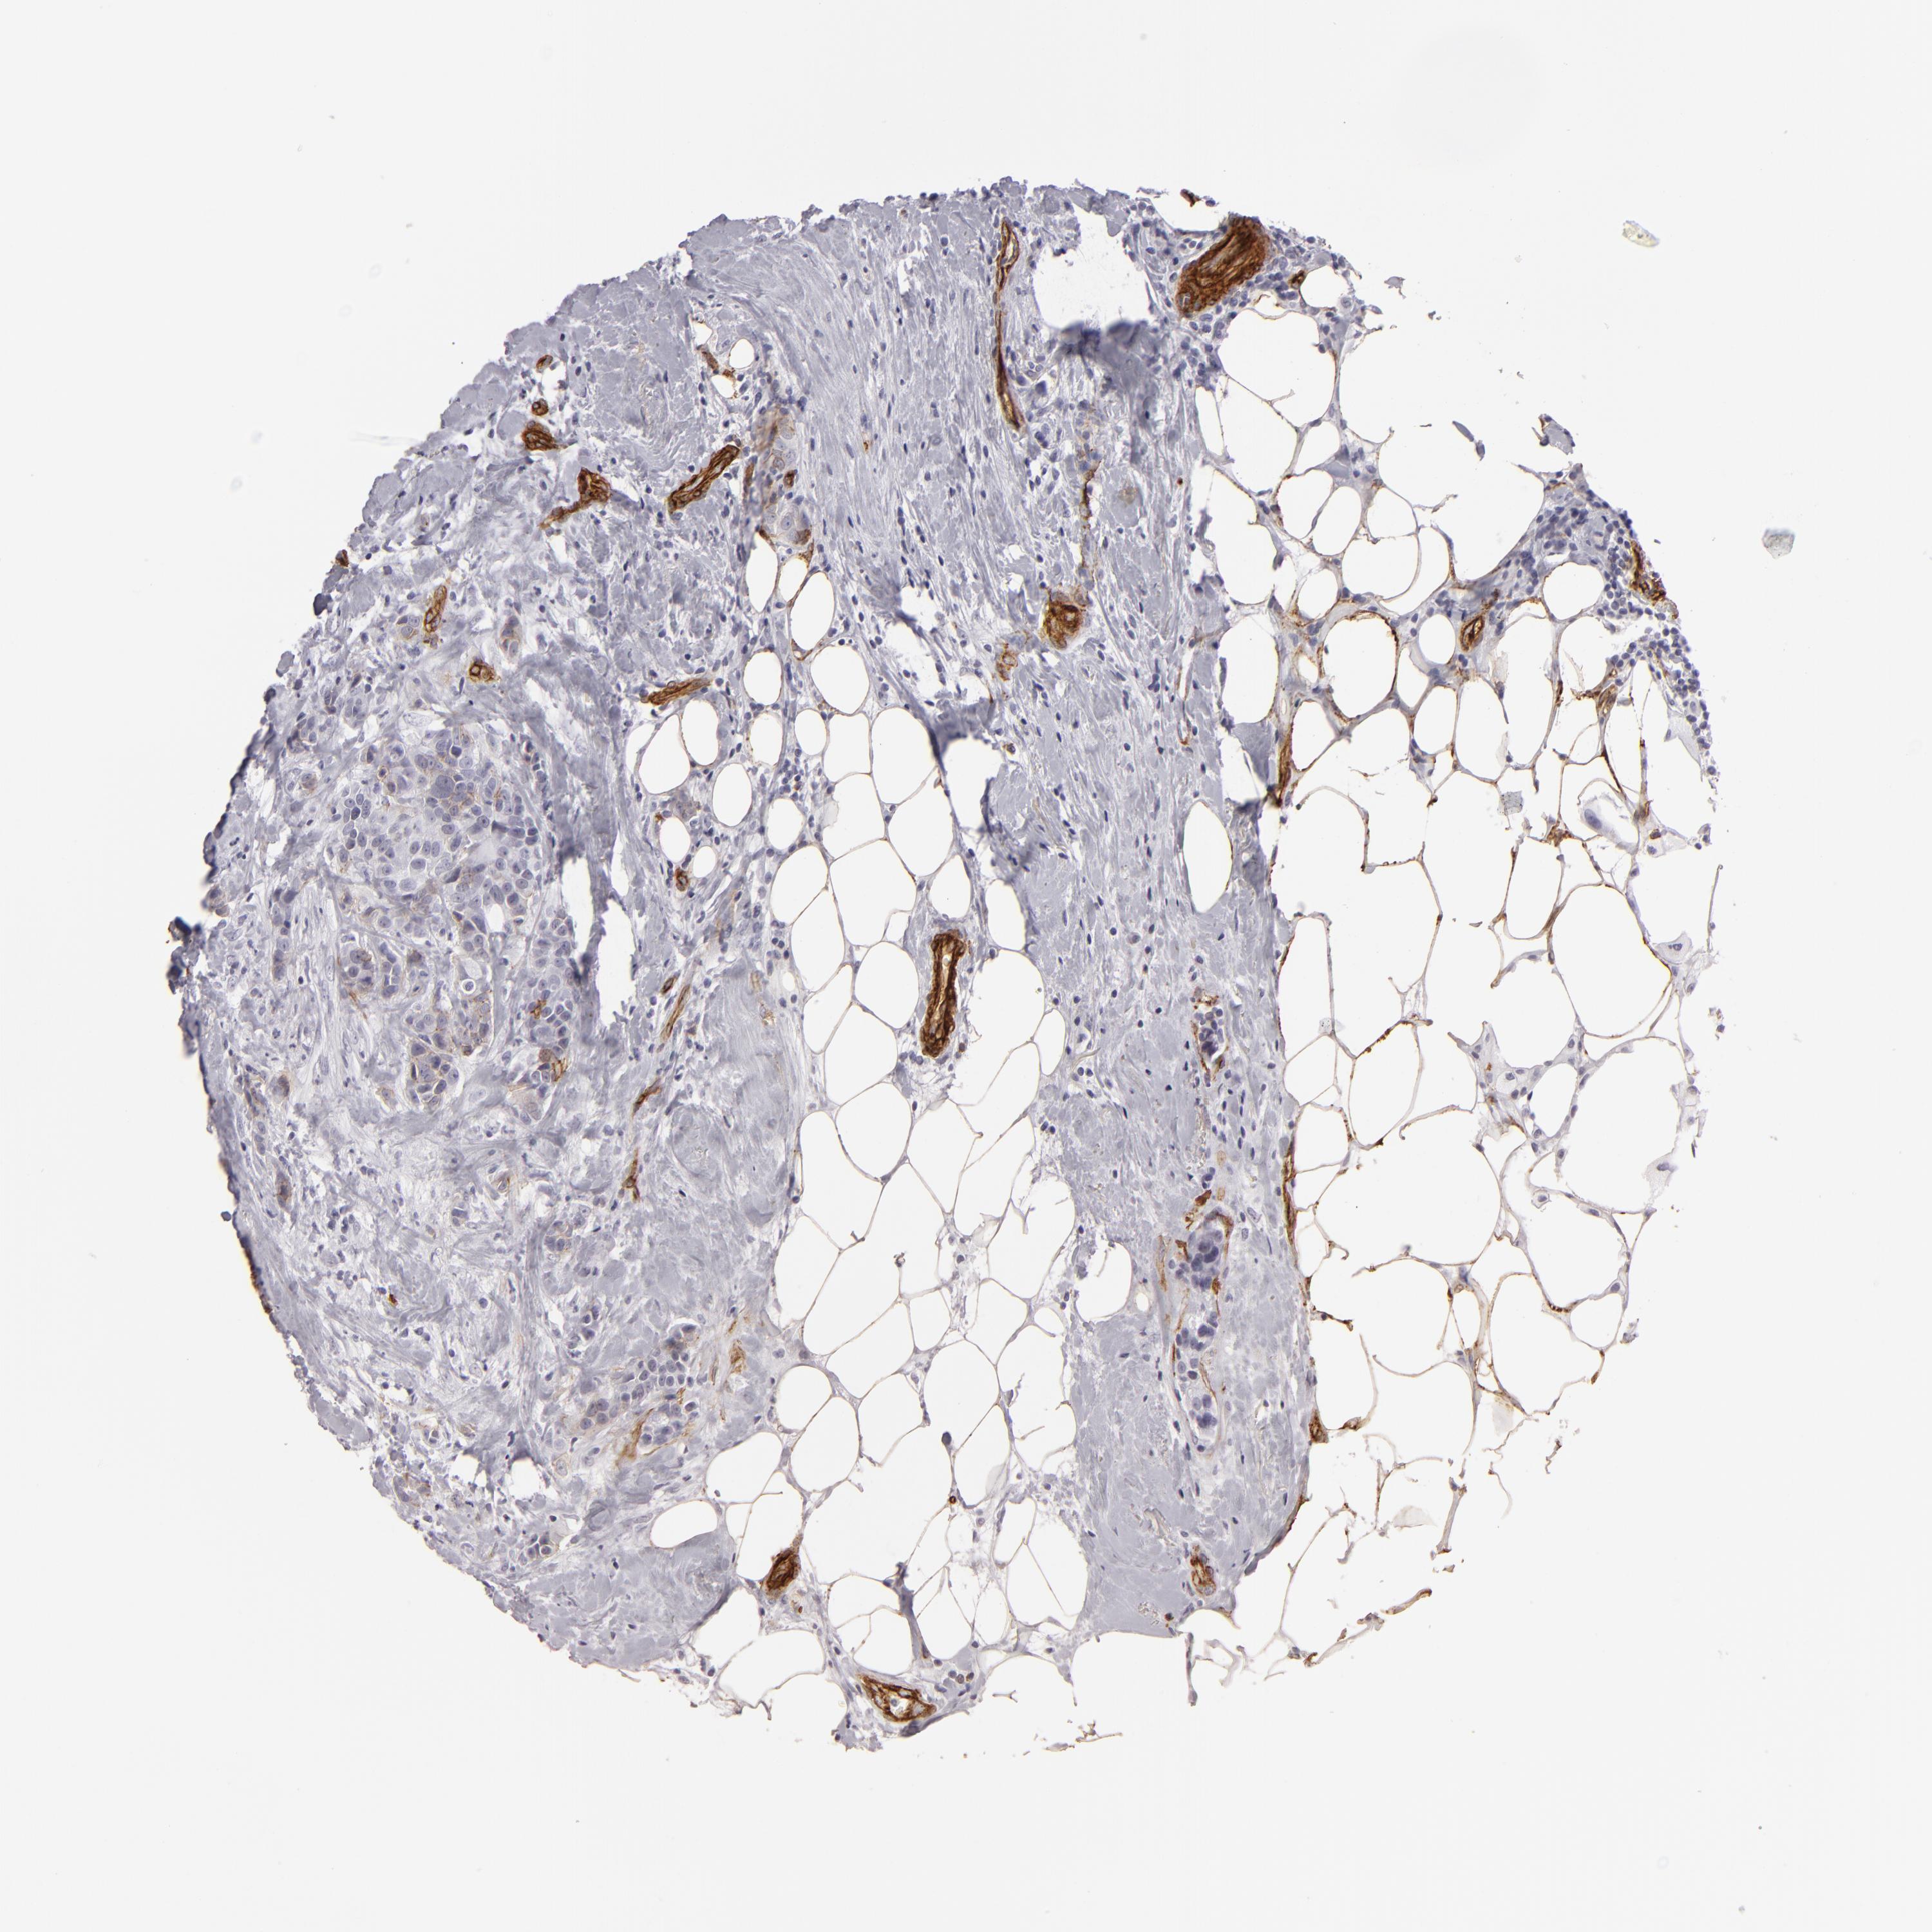

CANCER BREAST CANCER Show tissue menu

BRCA TCGA BRCA VALIDATION PROTEIN EXPRESSION